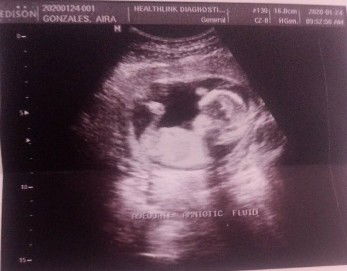

Is it normal po ba maranasan ng 24 weeks pregnant ang maramadaman ang heartbeat na malakas sa lower back but no pain po while lying in my bed?